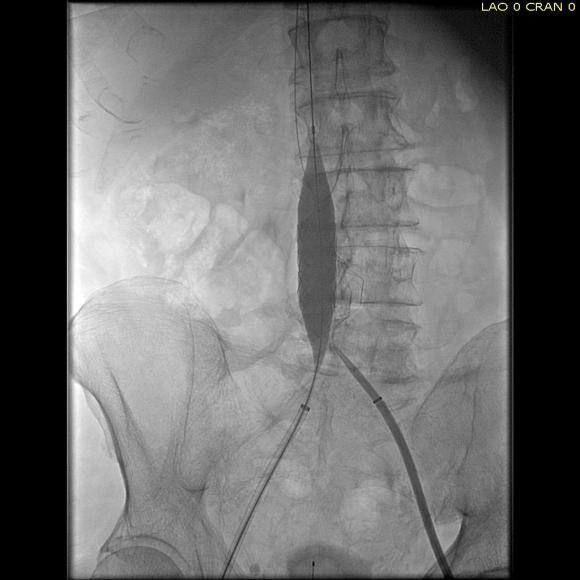

Once wire access is done, ballooning across the filter is done from both sides. A large sheath is them delivered across the IVC filter. Finally, a Palmaz stent mounted on a large balloon is delivered and deployed. I chose to do this from the right access, and retracted the wire on the left -something done with some trepidation because of the great difficulty gaining this access, but with with prior balloon dilatation, reaccess is made easier. Also, plan B would be reaccess from above.

intervention fig 4.png

After balloon dilatation of occlusion typically to 8mm from both sides, a sheath placed and Palmaz stent deployed across filter on a large 24mm balloon